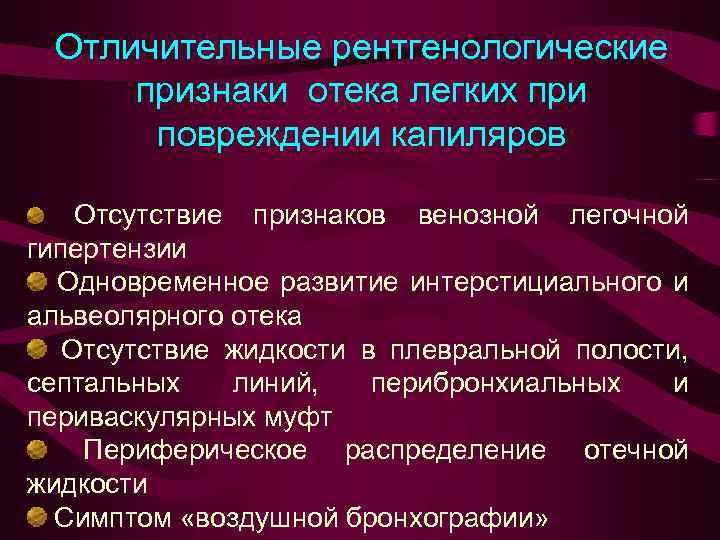

Отличительные рентгенологические признаки отека легких при повреждении капиляров Отсутствие признаков венозной легочной гипертензии Одновременное развитие интерстициального и альвеолярного отека Отсутствие жидкости в плевральной полости, септальных линий, перибронхиальных и периваскулярных муфт Периферическое распределение отечной жидкости Симптом «воздушной бронхографии»

Отличительные рентгенологические признаки отека легких при повреждении капиляров Отсутствие признаков венозной легочной гипертензии Одновременное развитие интерстициального и альвеолярного отека Отсутствие жидкости в плевральной полости, септальных линий, перибронхиальных и периваскулярных муфт Периферическое распределение отечной жидкости Симптом «воздушной бронхографии»